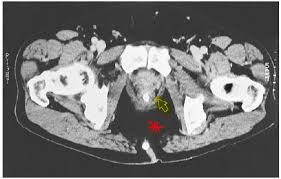

The Radiology Assistant Perianal Fistulas

The Radiology Assistant Perianal Fistulas from radiologyassistant.nl

Ct anatomy of the pelvis.

(1) the obturator internus and the piriformis, which are muscles of the lower extremity, and will be described with these (pages 476 and 477); This mri male pelvis axial cross sectional anatomy tool is absolutely free to use. Additional 3d anatomical images are available on the end of module, for a better understanding of gross anatomy of the dog, displaying 3d volume rendering of bones, splanchnology (liver, spleen anatomy of the male canine abdomen and pelvis on ct imaging: 0835 lotze anatomy of the pelvic floor. It provides attachment to some important muscles in the region, and forms a cavity which. Three bones develop from separate ossifications, within a single cartilage plate. The female reproductive tract 239. This mri male pelvis axial cross sectional anatomy tool is absolutely free to use. Ischial tuberosity which flexor of the knee attaches here? ƒ organs and structures of the female pelvis. The pelvis is a basin shaped bony structure formed by the combination of two pelvic bones (hip bones or innominate bones) and the sacrum. Ct anatomy of the pelvis. It is strengthened and supported by several joints and ligaments.